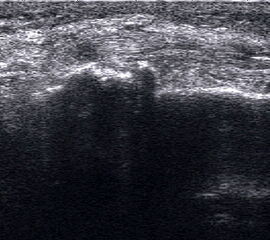

Längsschnitt über dem Lig. fibulocalcaneare. Die Peronealsehnen erscheinen als echoreiche runde bis ovaläre Struktur.

Abbildung 19

Lagerung: Rückenlage, OSG in Neutralstellung.

Schnittebene: LS über Lig. fibulocalcaneare.

Referenzstrukturen: Fibulaspitze und Talus.

Befunde: Das Lig. fibulocalcaneare is nativ schlecht abgrenzbar, da es in die Tiefe und nicht parallel zum Schallkopf verläuft. Direkt über das Band ziehen quer getroffen die Peronäussehnen. Durch die Distorsion kann auch das Peritendineum peroneale einreißen. Die Peronealsehnen sind dann in ihrer Sehnenscheide von Blut umgeben, was sich als echoarmer Ring (Halo-Phänomen) darstellt und ein indirektes Zeichen für eine Verletzung des Lig. fibulocalcaneare ist.